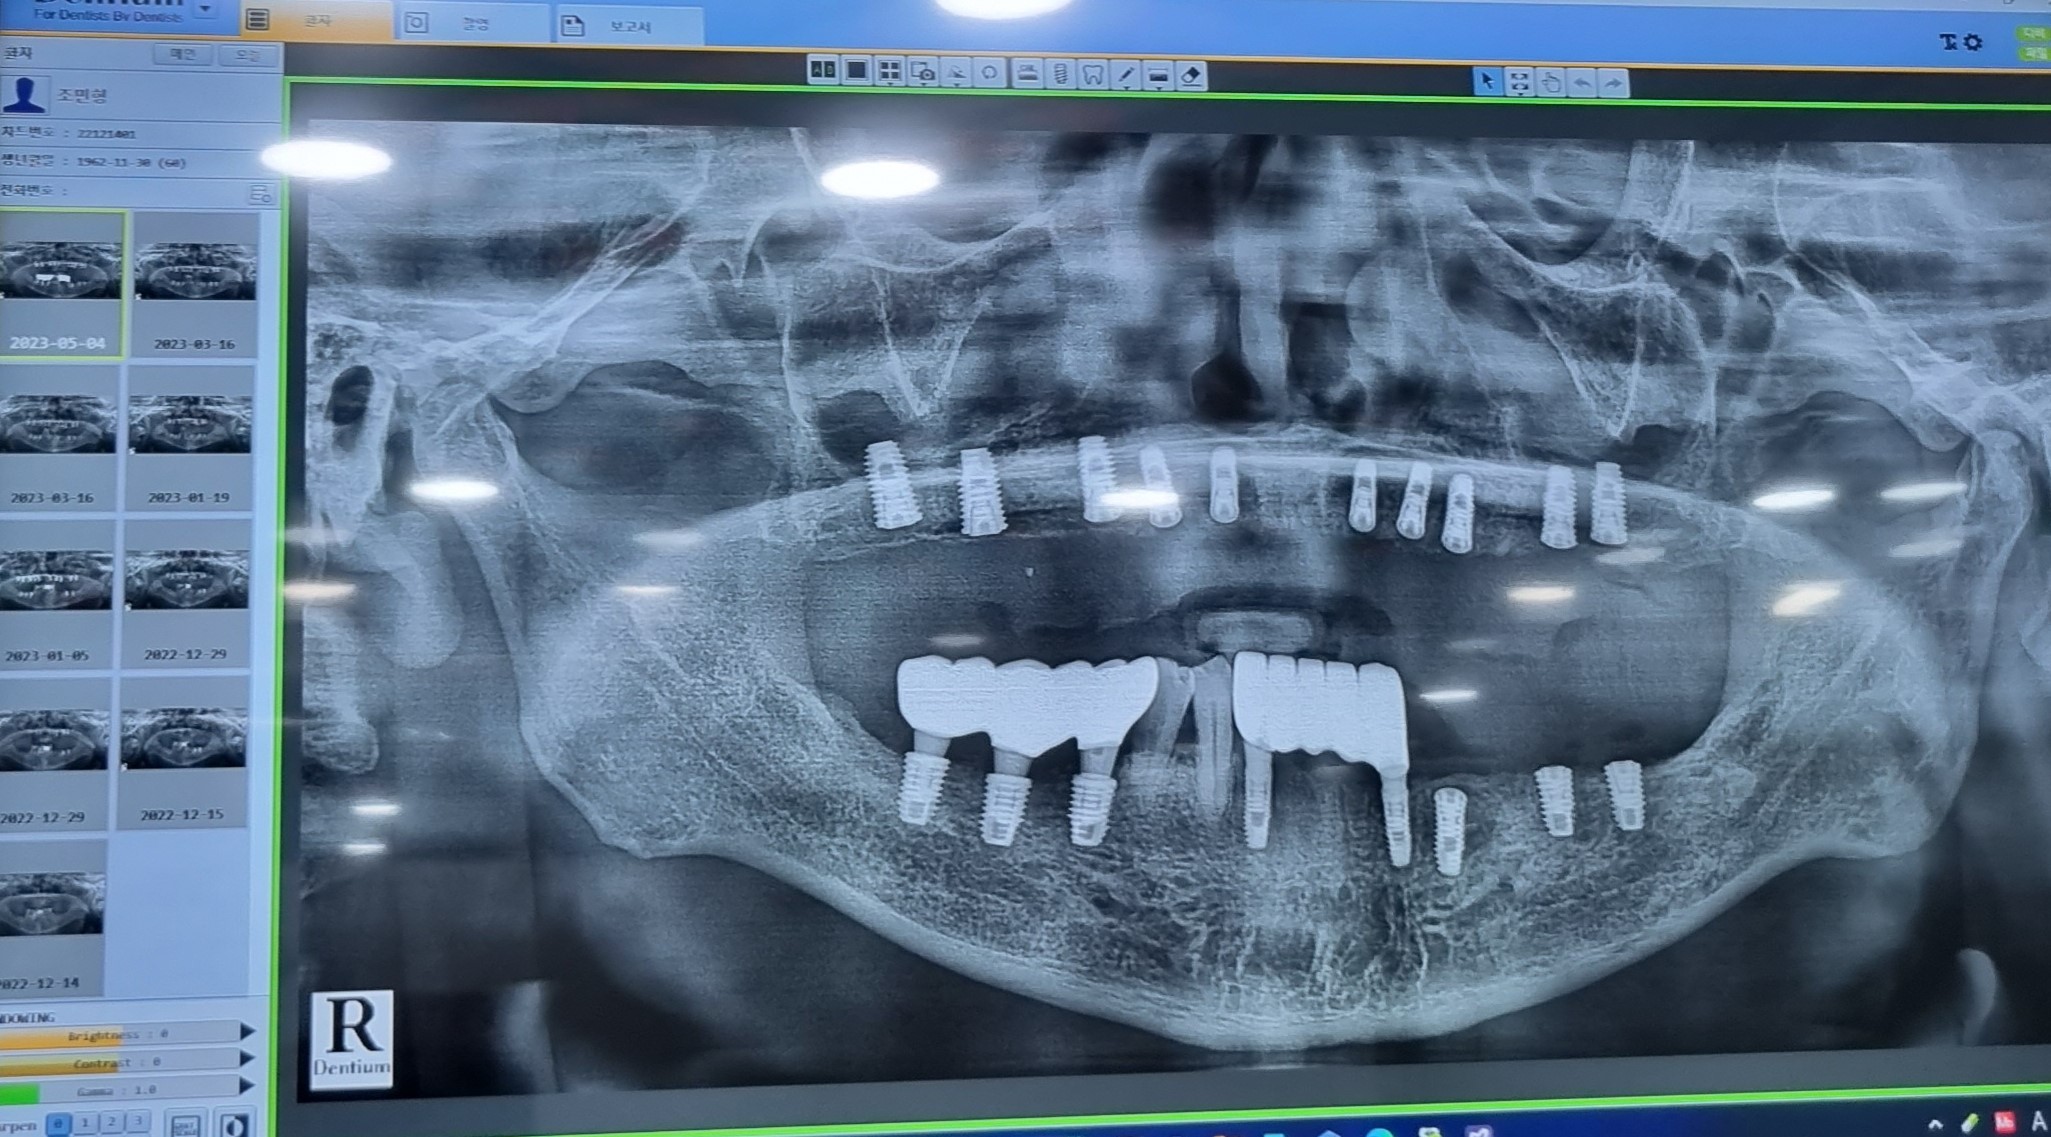

331아랫니下顎 45 48 47 42 33 2차시술을 하였습니다

420아랫니下顎 45 48 47 42 33

5 16 아랫니下顎 45 48 47 42 33   2차 수술

530아랫니下顎 45 48 47 42 33 보철을  올리는 날이였지요.

613아랫니 하악下顎 36. 37 41  2차 수술을 진행하였습니다.

6월  20아랫니 하악下顎 36. 37 41 치아齒牙 본뜨기

76하악下顎 36. 37 41 치아齒牙 본뜬후  2주가지나

드디어 하악下顎 보철을  올리는 날이였지요.

완성된  치아齒牙을  실제입안에  끼우고.

하악下顎 치아齒牙가  모두  완성되었습니다

당일  윗니上顎 10  2차  수술을  진행하였다

713상악上顎 13.12.22.23.24.26.27.14.16.17.치아를 본뜨기